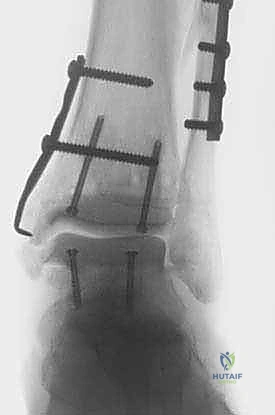

صور إضافية من داخل غرفة العمليات والخطوات الجراحية

ندرك أهمية توثيق الخطوات الجراحية لطلاب الطب والمرضى الراغبين في فهم دقة الإجراء. هذه الصور توضح مراحل زراعة وتثبيت الطعم العظمي الغضروفي بدقة متناهية تحت إشراف أ.د. محمد هطيف.